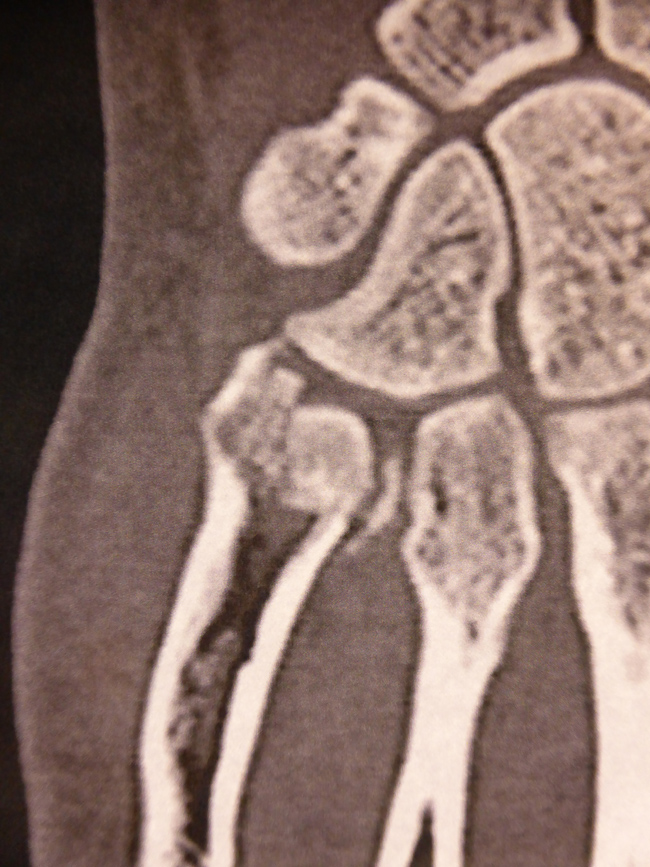

Les radiographies ne suffisent pas à un diagnostic précis.

Seul le scanner permet un examen détaillé.